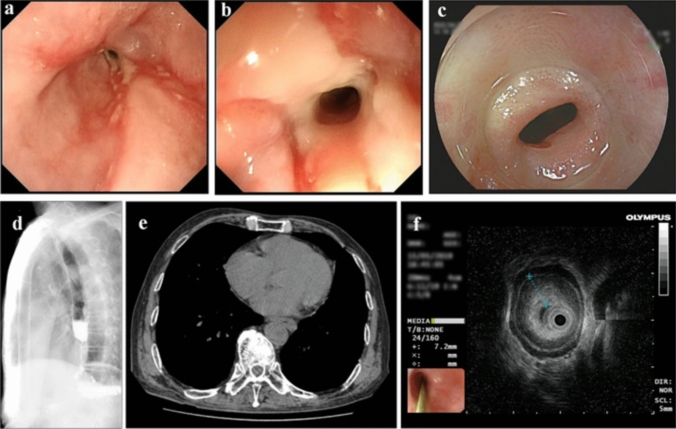

Background and aims: Endoscopic incision (EI) combined with triamcinolone (TAA) injection has emerged as an effective method for treating benign esophageal stricture (BES). However, a single EI and TAA injection seems to be insufficient for long-term relief of BES in some patients, especially those with recurrent BES. Here, we aimed to investigate the long-term efficacy and safety of repeated EIs and TAA injections in patients with recurrent BES.

Methods: Patients with recurrent BES who previously underwent endoscopic dilation or EI were enrolled in this retrospective study. All patients underwent multiple EIs and TAA injections. Patients were followed for at least 12 months. The primary outcome was the rate of re-stricture at 6 months after repeated EIs and TAA injections. The secondary outcomes included the symptom relief rate, the change in Stooler's dysphagia score (0, normal swallowing; 1, semidry food intake only; 2, soft food intake only; 3, fluid only; and 4, no oral intake) and body mass index (BMI) at 6 months, and overall adverse events (AEs). The risk factors for 6-month re-stricture were identified using logistic regression analysis.

Results: A total of 73 patients were enrolled in this study, including 30 (41.1%) with esophagogastric anastomotic strictures, 15 (20.5%) with caustic injury-related strictures, 14 (19.2%) who developed strictures after ESD, 5 (6.8%) with esophagojejunal anastomotic strictures and 9 (12.3%) with other types of strictures. A total of 264 EIs and TAA injections were performed, with 3 (IQR: 2, 5) treatments for each patient. The 6-month re-stricture rate was 53.4%, and the 2-month, 3-month, and 12-month re-stricture rates were 43.8%, 48.0%, and 54.8%, respectively. The 2-month, 3-month, 6-month, and 12-month dysphagia relief rates were 75.3%, 65.8%, 56.2%, and 54.8%, respectively. At 6 months after treatments, the median Stooler's dysphagia score had decreased from 4 (IQR: 4, 4) to 2 (IQR: 0, 4) (P < 0.001), and the median BMI had increased from 19.6 (IQR: 16.9, 21.8) kg/m2 to 20.8 (IQR: 17.4, 22.6) kg/m2 (P < 0.001). Bile reflux (OR 9.90, 95% CI: 0.99-98.43) and the number of EIs (OR 1.68, 95% CI: 1.17-2.41) were independently associated with 6-month re-stricture after repeated EIs and TAA injections. Four EI-related perforations were successfully treated with a covered metal stent (n = 3) and rescue surgery (n = 1).

Conclusions: Repeated EIs and TAA injections were effective and reasonably safe in managing recurrent BES. However, the long-term efficacy remains suboptimal, thus further investigations are needed.